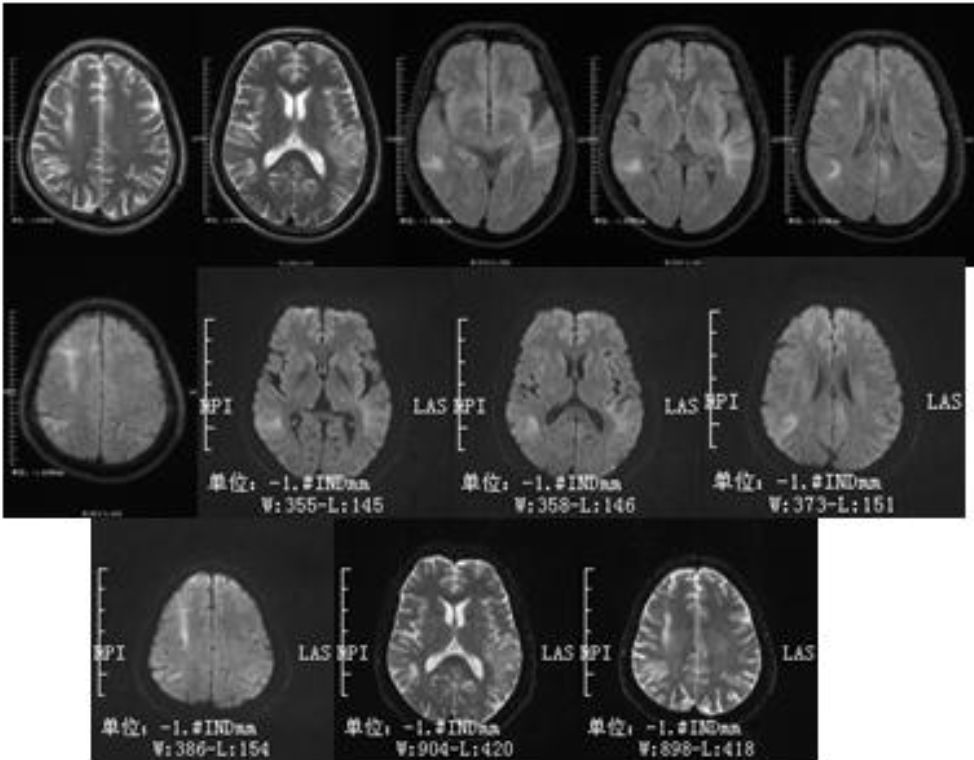

63岁男性,右侧肢体无力3小时入住某医院,因肢体无力加重转入。既往有高血压病、脑干出血病史。外院头影像学检查如下:

影像学可见:双侧侧脑室旁散在片状、卵圆形长T1长T2信号,其中左侧半卵圆中心病灶等T1,长T2信号,DWI呈高低不等混杂信号,结合病史,考虑为此次责任病灶。MRA并未见明显畸形或狭窄。

后补充CT:

诊断: 脑出血。

病例讨论:

该病例再次印证了CT是急性卒中的首要检查。因为MRI出血判读过于复杂,甚至可能模拟梗死,给治疗带来挑战。